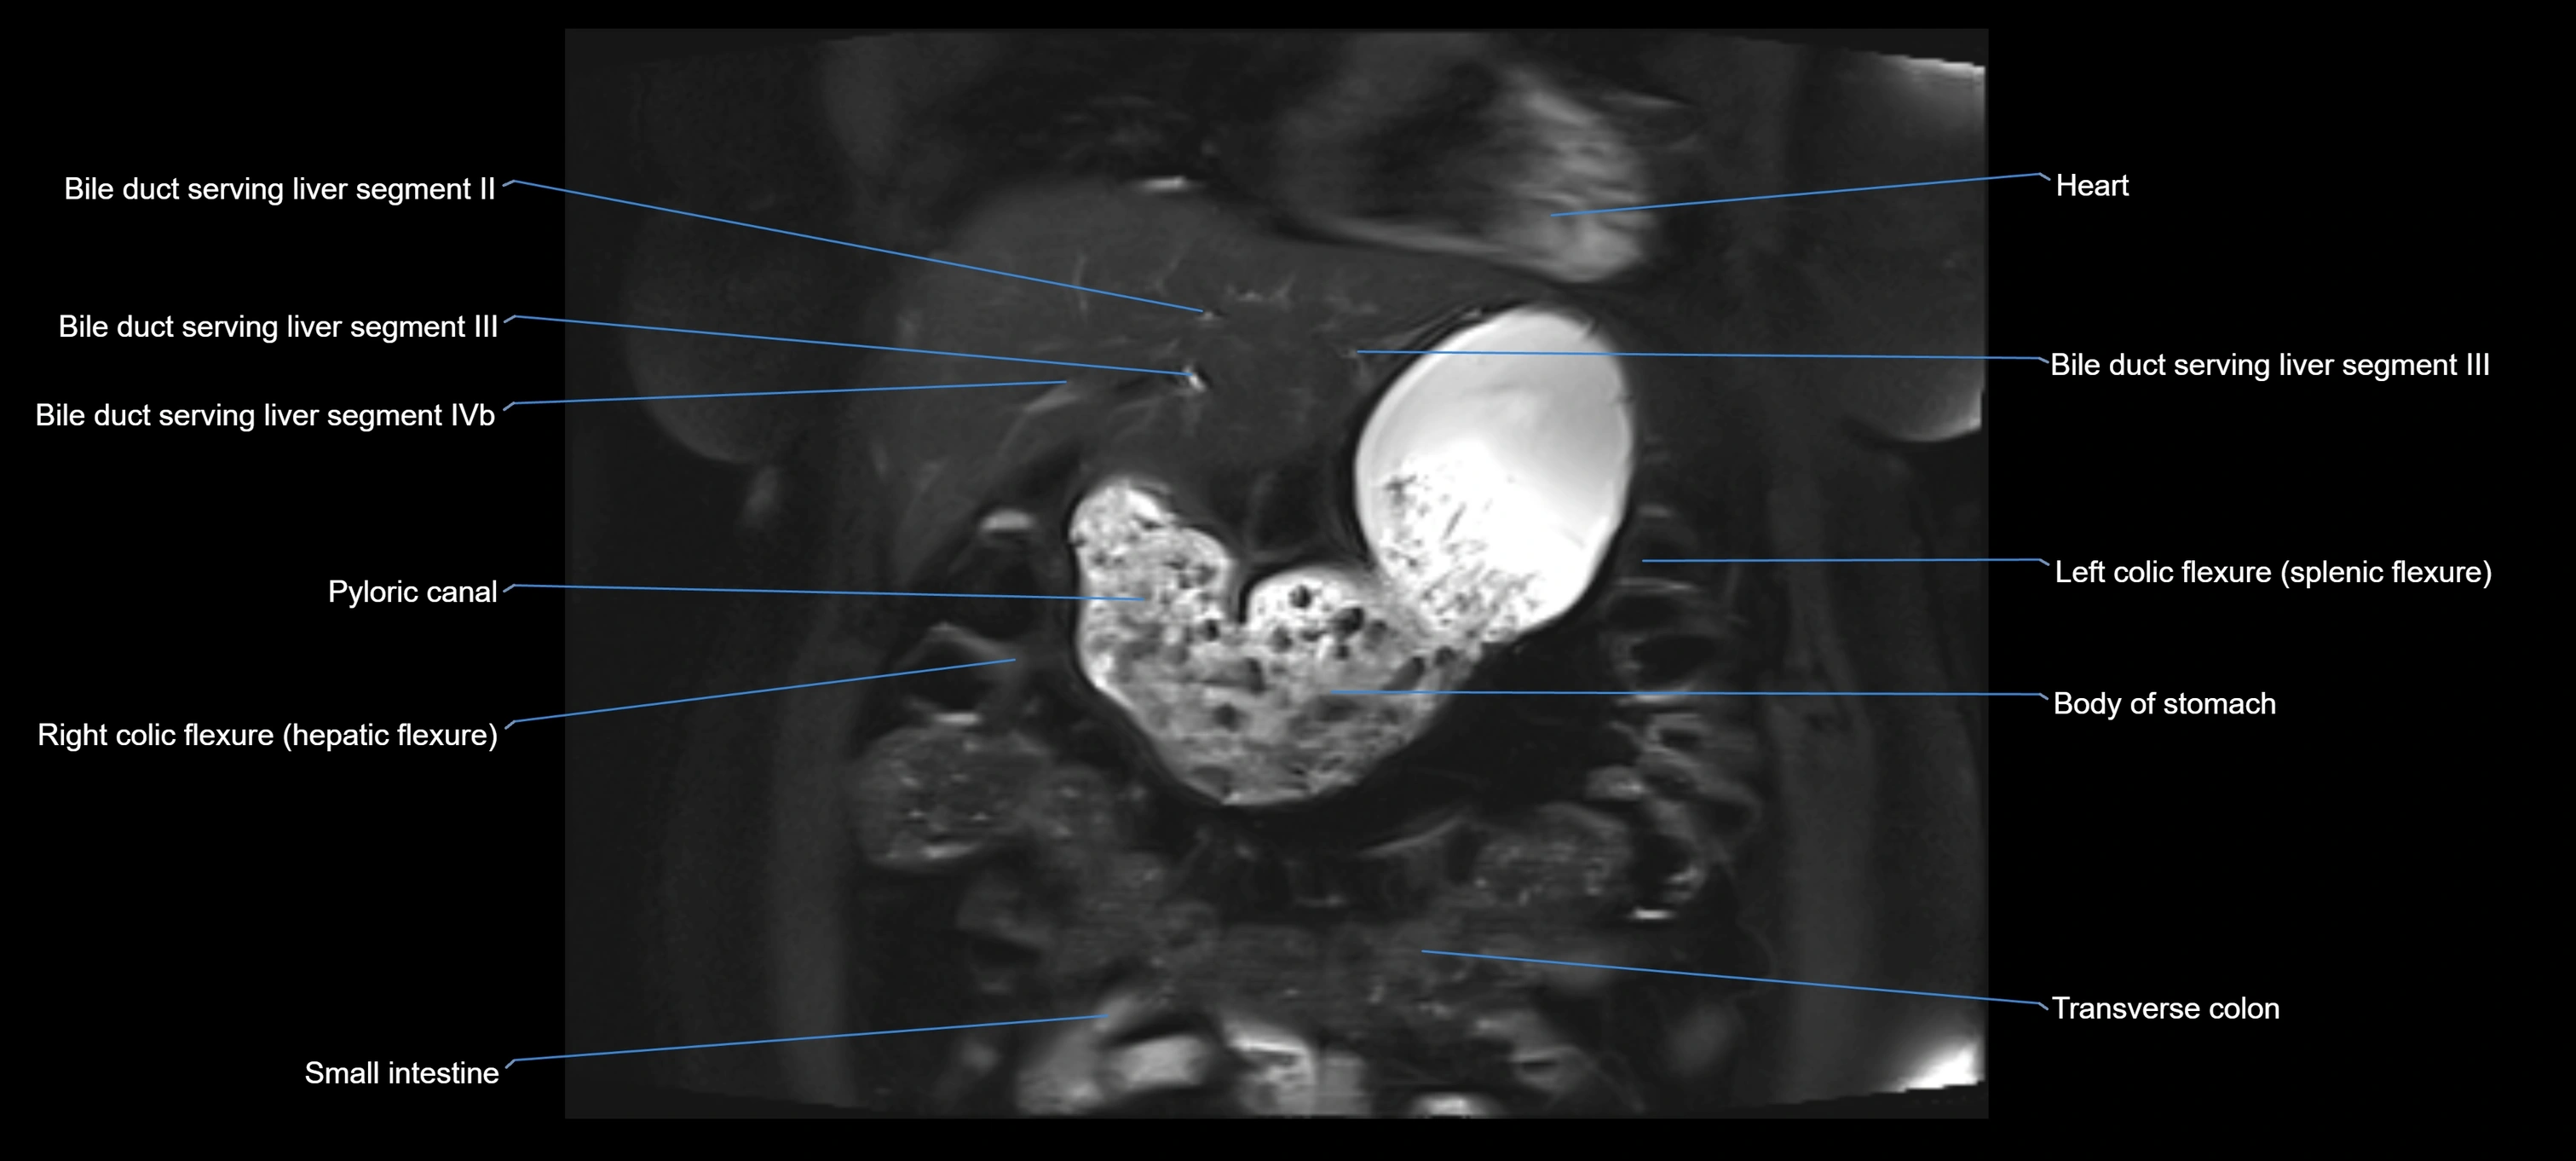

MRI image

image